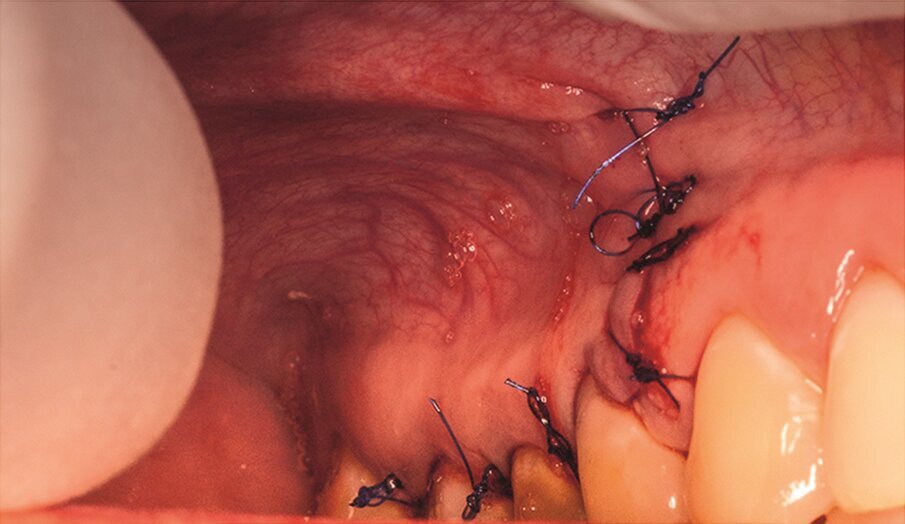

Fig. 1j: Finally, the cortical window was replaced and stabilised with collagen tape.

Under local anaesthesia, a full thickness mucoperiosteal flap was reflected and the printed template was used to mark the cortical window, which was cut with a Piezotome CUBE LED handpiece (ACTEON), removed (Figs. 1e–h) and then placed in sterile saline. An apicectomy was done (Fig. 1i), and the mesial canals were retro-prepared with ultrasonic tips (NSK) and filled with EndoSequence BC RRM Fast Set Putty (Brasseler). The cortical window was then placed back and stabilized with collagen sponges in the gaps (collagen tape, Zimmer Biomet; Figs. 1j & k), and the ‑ap was sutured using 6/0 prolene suture material (Corpaul).